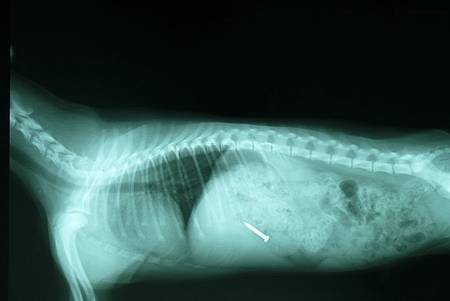

魚鉤、針、鐵釘、雞骨頭等尖銳的異物,可能

會刺穿消化道,使消化道內的細菌與食物進入體腔,

造成感染,引起腹膜炎、敗血症,甚至死亡。

診斷異物的方法,消化道x光檢查是必須的,

x光檢查分為一般攝影與照影劑攝影,石頭、鐵釘、

針,等...這些密度較高的物品,在一般x光攝影就

可以診斷出來,但是如果是線、水果籽如:龍眼、

桃子、酸梅等...、塑膠密度較小的物品,就無法在

一般x光攝影下被檢查出。

動物吞食了鐵釘與耳環的x光片(嘉興動物醫院)